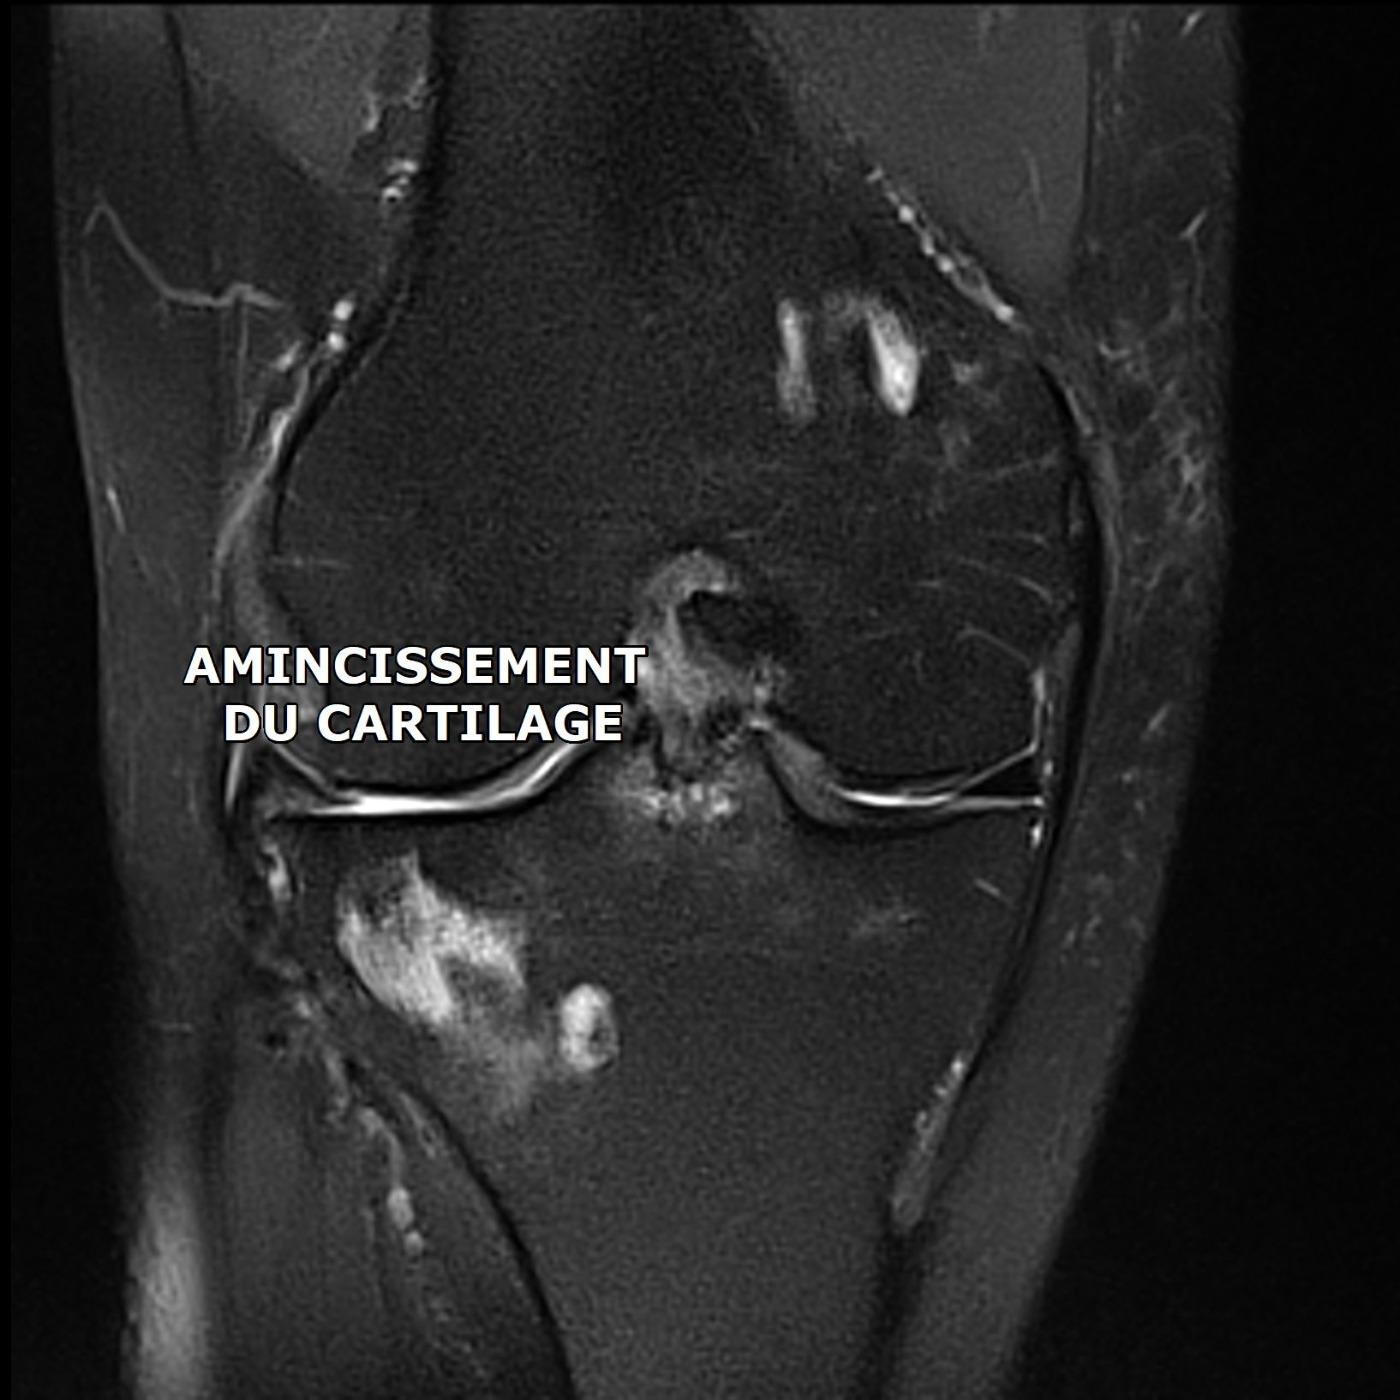

VISCO SUPPLEMENTATION POUR ARTHROSE DU GENOU

L'IRM du genou de cette patient de 64 ans montre un amincissement marqué de l'épaisseur du cartilage du compartiment fémoro tibial externe. Devant la persistance de douleurs invalidantes, son médecin a prescrit une infiltration de corticoïdes et une viscosupplémentation (injection d'acide hyalruonique).

La procédure a été réalisée sous contrôle radiographique.

Il est recommandé d'observer une repos articulaire pendant les 48 heures qui suivent l'injection.